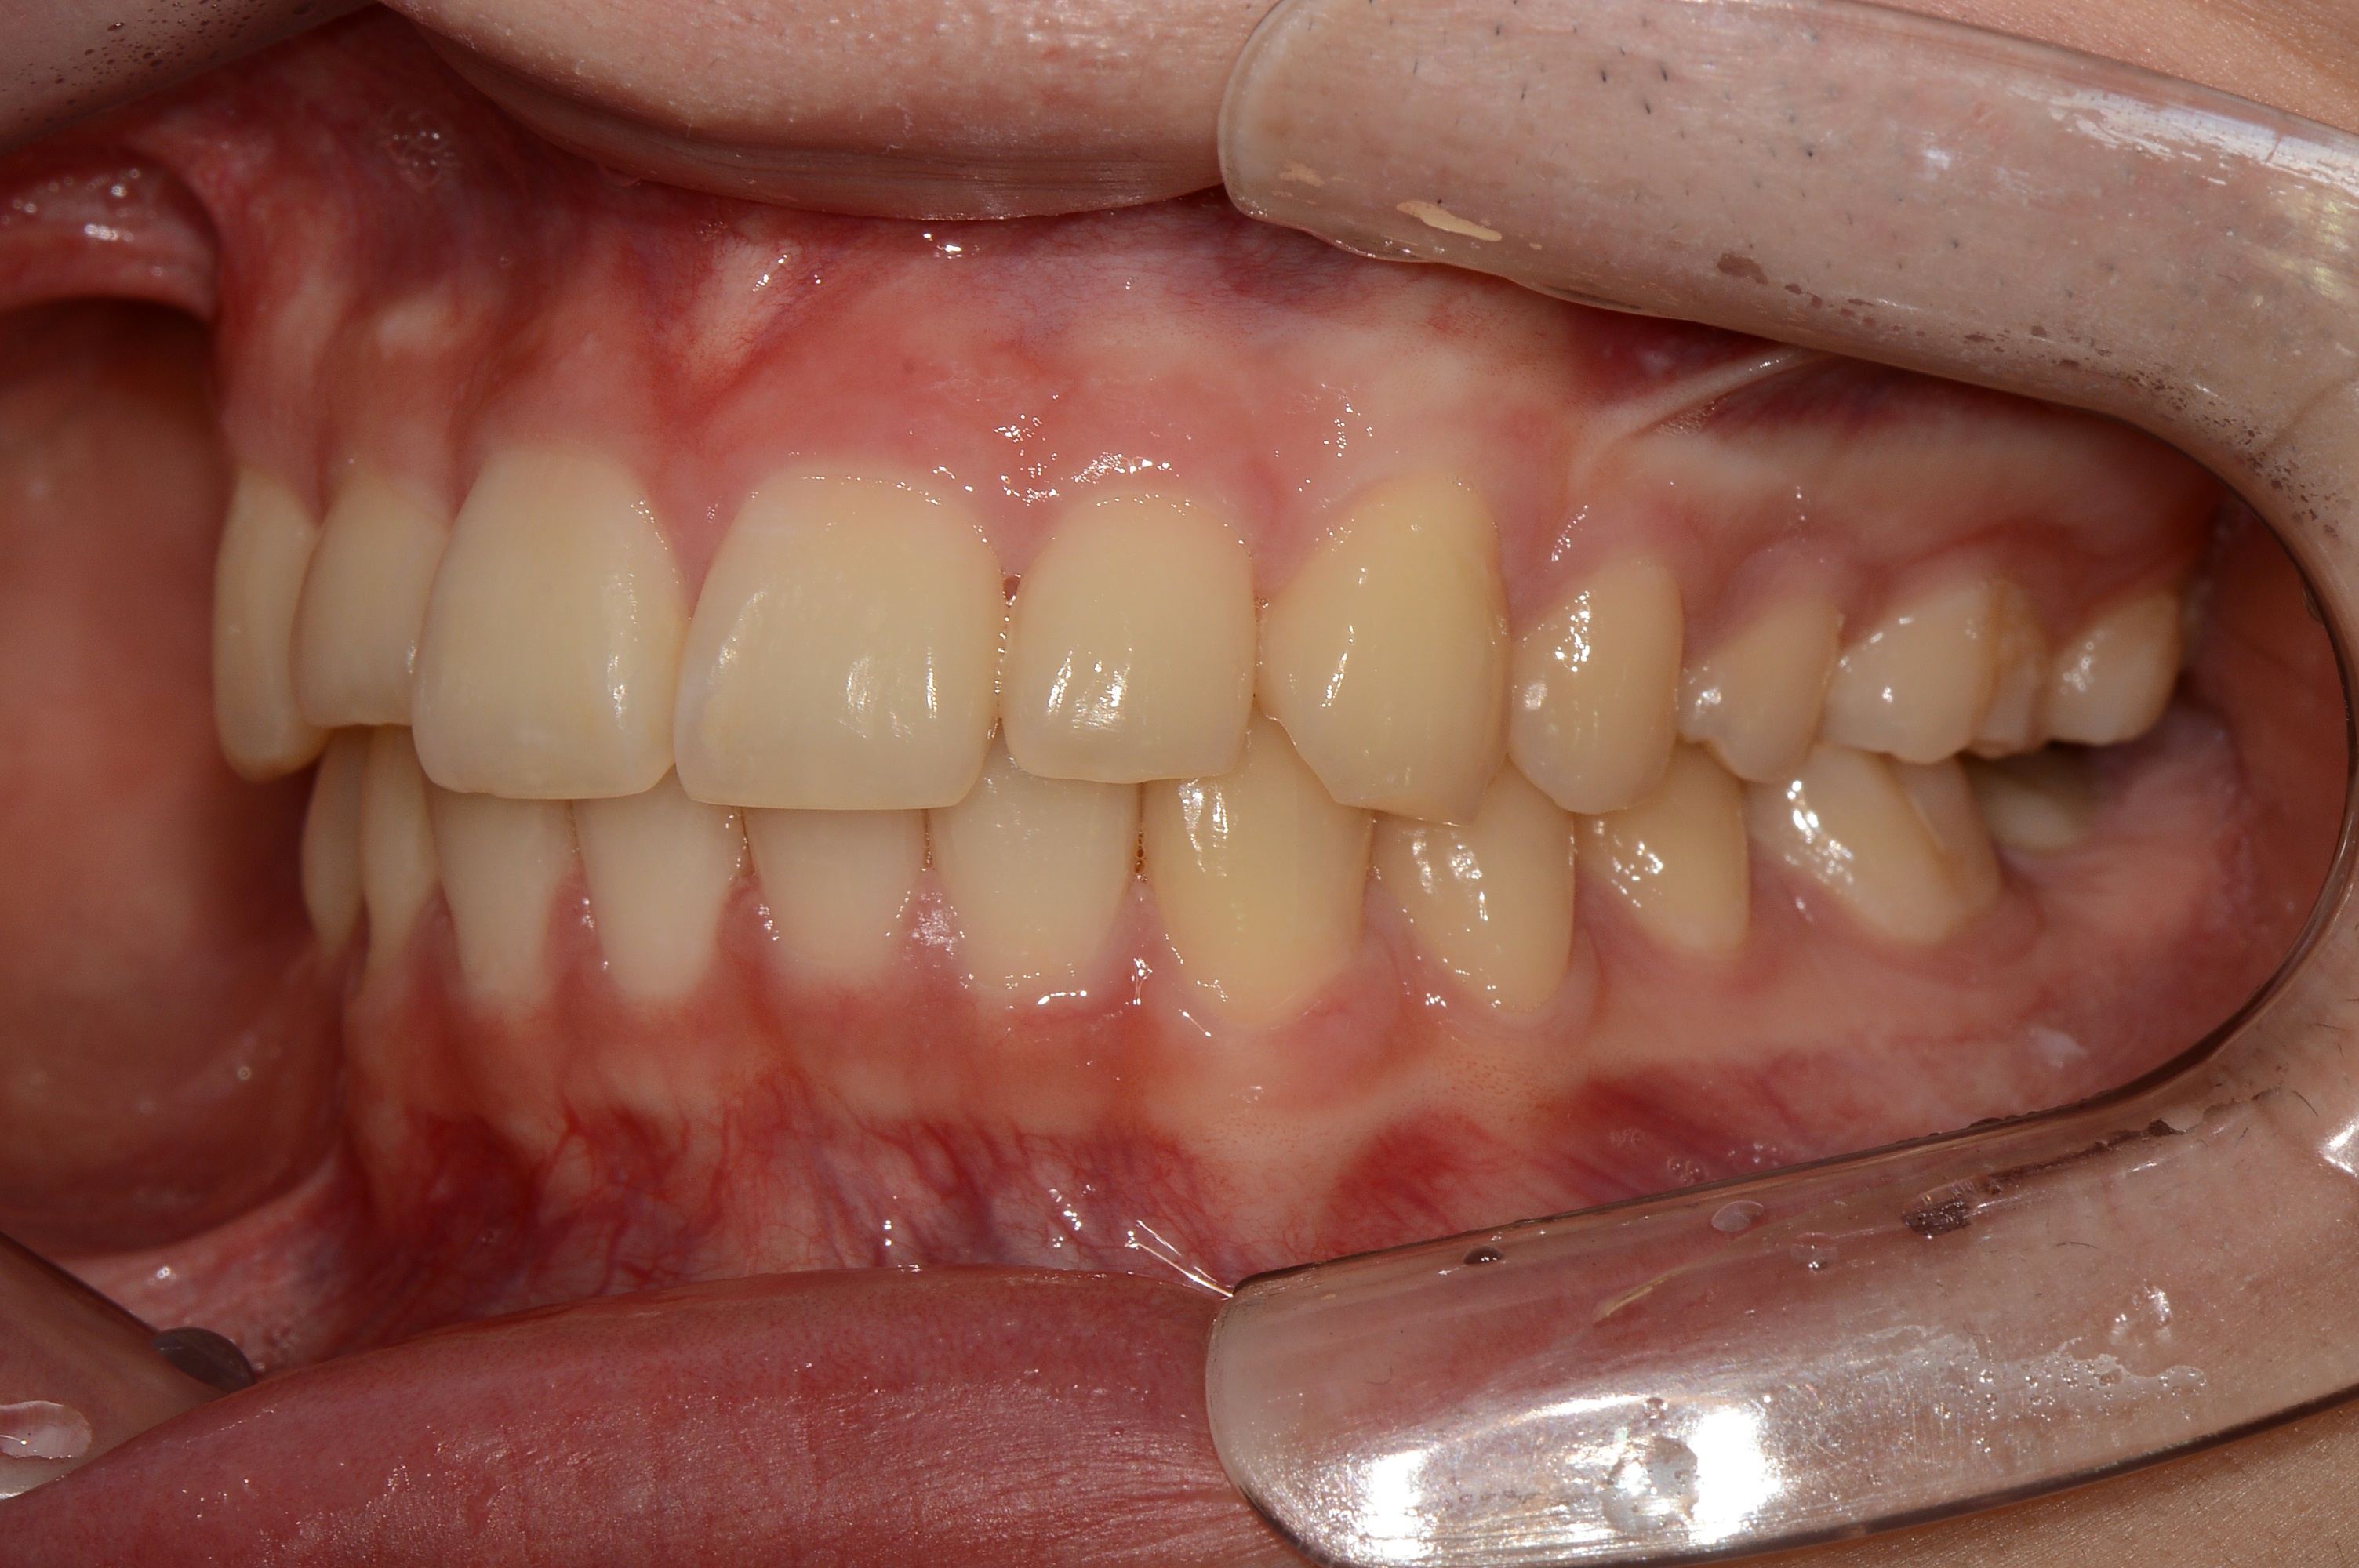

치료 전 사진입니다.